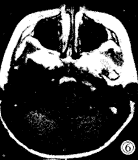

图1-3 女性,5岁,脑干明显增大膨突,横断面T1W低信号(图1),T2W高信号(图3),无明显强化(图2),肿块向前包绕基底动脉,向后推移第四脑室。图4-6 女性,6岁,横断面T1W低信号(图4),矢状面T1W增强(图5), 横断面T1W增强(图6),片状不均匀强化灶中见结节样强化。图7 男 性,6岁,横断面T1W增强,肿块环状强化呈葫芦形,中央低信号灶不强化。图8 女性,2岁,矢状面T2W,肿块向后压迫中脑导水管,第三脑室、侧脑室积水明显。

MRI:鉴于无颅骨伪影和多方位成像特点,MR是目前诊断胶质瘤和准确定位的最好方法,对于治疗计划的制定和随访有很大帮助,特征性MR表现为脑干胶质瘤呈膨胀性生长(图1~3),多为实质性,在T2加权图像上显示最为清楚,为明显高信号(图3),在T1加权图像上为低信号或低、等混合信号(图4),注射GD-DTPA后多数病灶 明显增强,少数无明显增强(图1~2),强化方式有:弥漫型(图未列出)、结节型(图4 ~6),沿着肿瘤边缘或囊变坏死区呈环状(图7)。肿瘤边界多较清楚,周围脑组织水肿多 较轻或不明显,肿瘤内部可发生小囊变或小出血灶,肿瘤向前生长包埋基底动脉(图1~3) ,部分脑干胶质瘤可位于中脑导水管附近,虽然较小,但可造成对中脑导水管的压迫,而继 发脑积水[3](图8),MRI较CT能更好地明确占位性病变的性质、部位、范围。